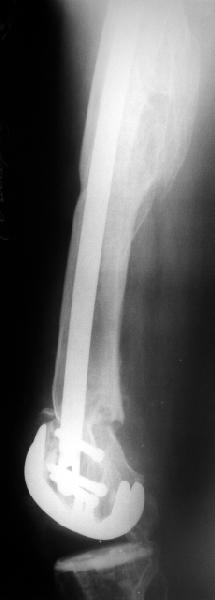

Alexander Chelnokov 02 Июнь 2004, 13:45

В итоге сделали антеградный остеосинтез. В дистракторе свежий перелом вправился сразу, а вот старый - оставил проблему, дистальный отлмомк остался все равно кзади. И гвоздь бы прошел кпереди от него, а ретроградный - перфорировал бы передний кортекс. Так что пришлось еще сделать чрескожную остеотомию через перелом, чтобы малость мобилизовать дистальный отломок. Снимки в прилжении.

Критика, комментарии, мнения?

The radiographs look excellent and a good outcome would be anticipated. The idea to osteotomize the femur shaft to compensate for the prior shaft malunion was clever and should work fine.

I can't actually see the osteotomy on either radiograph. Is it more proximal than we see in these radiographs or so well aligned as to be not visible?

TAC> idea to osteotomize the femur shaft to compensate for the prior shaft malunion

TAC> was clever and should work fine.

The "idea" was an emergency appeared when the nail tip proceeded to the fracture level and became targeting anteriorly to the distal fragment.

TAC> I can't actually see the osteotomy on either radiograph. Is it more proximal

TAC> than we see in these radiographs or so well aligned as to be not visible?

The osteotomy was perfromed trough the fracture site. See the image.